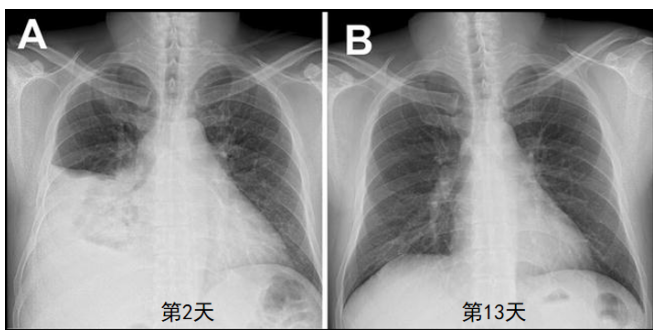

对于重症腺病毒肺炎,抗病毒药物主要包括西多福韦/西多福韦脂质体、利巴韦林、更昔洛韦、干扰素。(1)西多福韦:DNA聚合酶抑制剂,体外对所有亚型敏感。该药目前在国内尚未上市,美国FDA批准其用于重症腺病毒肺炎的治疗。用法:5 mg/kg+100 ml生理盐水静滴1~2 h。当血肌酐>133 μmol/L,CrCI≤55 ml/min,尿蛋白≥100 mg/L(尿蛋白++)时严禁使用。因为该药对肾功能损害较大。2015年韩国一项回顾性研究发现,在非免疫功能低下的腺病毒肺炎成人患者中,早期给予西多福韦治疗或许是疾病完全缓解的重要因素[7]。2020年新加坡的一篇病例报告显示,1例成人重症腺病毒肺炎患者在第1天和第8天使用静脉西多福韦,最终顺利拔管,成功救治[8]。这也增强了我们对西多福韦治疗成人重症腺病毒肺炎的信心。2021年韩国另一项研究纳入22例重症腺病毒肺炎患者,其中13例使用西多福韦,9例未使用西多福韦,结果发现西多福韦不能改善免疫功能正常重症腺病毒肺炎患者的临床结局(包括平均住院时间、住ICU时间、使用机械通气及ECMO的概率)[9]。因此,西多福韦在重症腺病毒肺炎中的临床应用需更多大规模随机对照研究验证。(2)利巴韦林:利巴韦林是鸟苷的核类似物,具有抗DNA和RNA病毒的体外活性。其作用机制包括病毒聚合酶的抑制,病毒RNA加帽,以及新合成DNA中突变率的增加。体内有无活性存在争议,仅对C型有效。用法:0.4~0.6 g q12h。主要不良反应为消化道症状、溶血性贫血。2017年一篇文献报道了1例39岁男性重症腺病毒病例,口服利巴韦林第4天,患者血小板回升,体温降至正常,呼吸困难明显改善。第2天和第13天的胸部X线片可见肺部病灶明显吸收,治疗效果非常理想(图7)[10]。(3)更昔洛韦:该药是DNA聚合酶抑制剂,体外有活性,但作用弱于西多福韦。1989年体外试验发现更昔洛韦对肝移植患儿分离的腺病毒生长有抑制作用[11]。研究证实更昔洛韦能够抑制HAdV5型的复制,且减轻叙利亚仓鼠模型中HAdV 5型感染引起的病理变化[12]。还有研究发现对于肾移植受者腺病毒所致出血性膀胱炎有效[13]。但仍需大型RCT研究证实其对腺病毒感染的疗效,探索减少不良反应的方案。(4)干扰素:目前认为干扰素对于AdV 7型和3型的敏感性较强。用法包括:肌注、静滴、皮下注射、雾化吸入和滴鼻。需要注意的是:干扰素应早期、足量应用。在重症感染初期,促炎反应及抗炎反应常同时发生。不同免疫应答决定重症感染患者的预后。因此,在治疗重症腺病毒肺炎时,需动态监测IL-6、IL-10、HLA-DR、T细胞、B细胞,评估患者的免疫状态,明确患者促炎反应占优势还是抗炎反应占优势,进而决定治疗策略。(1)糖皮质激素:糖皮质激素在重症腺病毒肺炎中主要发挥抗炎作用,其能够抑制过强的免疫反应,减轻严重病例的损伤。2006年,Takahashi等报道了1例重症腺病毒肺炎合并高细胞因子血症,患者高热(体温最高40℃),乳酸脱氢酶(LDH)、铁蛋白升高,甲强龙冲击治疗3 d后,患者体温下降,呼吸窘迫症状迅速得到改善,LDH及血清铁蛋白也明显下降[14]。国内文献显示,静脉短期使用大剂量糖皮质激素对于改善中毒症状及减少肺部渗出有益,早期激素治疗或许能够阻断肺纤维化或闭塞性细支气管炎的疾病进程[15]。国内相关指南及指导意见也推荐[16, 17],对于持续高热(体温≥39℃),肺部多发或大片实变,短期进展迅速,明显呼吸窘迫,达到急性肺损伤(ALI)或急性呼吸窘迫综合征(ARDS)诊断标准的患者,可以使用糖皮质激素。推荐用量:氢化可的松3 mg/kg,甲泼尼龙80~320 mg/d,地塞米松0.5~1.0 mg/kg,1~3 d,动态评估患者的免疫状态及病情。用药期间注意加强护胃,避免骨缺血及继发感染。我科在使用糖皮质激素时,多数患者都会加用丙种球蛋白。(2)丙种球蛋白:丙种球蛋白的作用主要在于:①调节机体免疫,预防二重感染,减少耐药菌感染或院内感染的发生;②中和抗体,丙种球蛋白中可能含有病毒的中和抗体,能够加速呼吸道中腺病毒的清除。用法:剂量400 mg/(kg·d),连用3~5 d或1g/(kg·d),连用2 d。(1)氧疗:安静状态下无缺氧表现,也予持续鼻导管吸氧;低氧血症者,予高流量氧疗/面罩,SpO2>93%。(2)无创通气(NIV):呼吸频率>30次/min或吸氧5 L/min,SpO2仍<93%,NIV 1~2 h无改善,应及时转为有创通气。(3)有创通气:无创通气失败或不耐受,氧合指数<150 mmmHg,双肺浸润,需行有创通气,可予低潮气量通气(6 ml/kg理想体重);单侧肺,“健侧肺向下”;如果没有禁忌证,也可行俯卧位通气。对于重症腺病毒肺炎,主要以综合治疗和对症支持为主,因此病情的监测至关重要。病情监测包括,①生命体征,如体温、脉搏、呼吸频率、血压、咳嗽气促症状;②出入水量:重症病毒性肺炎患者都存在容量性肺水肿(湿肺),此种情况需予以液体负平衡,有利于稳定氧合;③实验室检查指标:心肌酶,肝肾功能,凝血功能,CRP,PCT,腺病毒DNA滴度,铁蛋白,KL-6,血气指标,IL-6,IL-10,TNF-α,淋巴细胞亚群;④影像学:每2~3 d复查一次床旁胸部X线片。(1)发热、咳嗽:如果患者体温过高,建议物理降温或在必要时使用药物退热。如果患者咳嗽剧烈,需要考虑是否与纵隔气肿有关,如果是干咳,可以酌情给予镇咳治疗。(2)脏器支持:床旁CRRT/血液灌流、护肝、护心等。(3)营养支持:提倡高蛋白、低碳水化合物饮食,优先肠内营养。(4)精神障碍:积极进行心理疏导,必要时予以抗焦虑药物。(1)混合感染:若患者在治疗过程中一直没有好转,或者短暂好转后又恶化,出现脓性痰/胸水,WBC升高,NAP升高,或者抗生素治疗无效,此时需考虑混合感染可能,早期混合感染以肺炎链球菌、支原体、流感病毒为主;后期感染尤其是机械通气患者,多为铜绿假单胞菌、鲍曼不动杆菌和曲霉感染;对于免疫缺陷患者,需警惕巨细胞病毒和耶氏肺孢子菌感染。国内文献显示,对于混合感染,主要为非典型病原体感染以及其他一些呼吸道病毒感染较为常见。(2)脑炎:最常见为7型和3型腺病毒感染导致,患者有神志改变,如神志淡漠,此时应予对症处理,随着病情的好转,脑炎相关症状会逐渐缓解。(3)心力衰竭:主要为感染中毒性心肌炎,这种情况需要严格液体负平衡,同时予以抗心衰治疗。2017年的国外的一篇文献报道了采用西多福韦联合ECMO治疗腺病毒所致ARDS,该文献仅有3例患者,第1例和第2例患者都是在给予机械通气后很快启动ECMO,在第1天至第28天,ECMO也发挥了一定的作用,第2例患者在第30天死于临床并发症。在机械通气时联合ECMO或许能够改善重症腺病毒肺炎患者的预后,但需要积极防治并发症。该文献还分析了15例重症腺病毒肺炎患者使用ECMO的情况,结果发现早期ECMO联合西多福韦在改善患者死亡率方面有一定作用[18]。2016年的一篇文献报道了早期ECMO联合CRRT成功救治2例腺病毒所致ARDS患者的经验[19]。这2例患者成功救治的关键在于:①患者在机械通气后很快启动ECMO;②联合CRRT治疗,保守的液体管理,严格控制出入量;③尽早给予抗病毒药物。